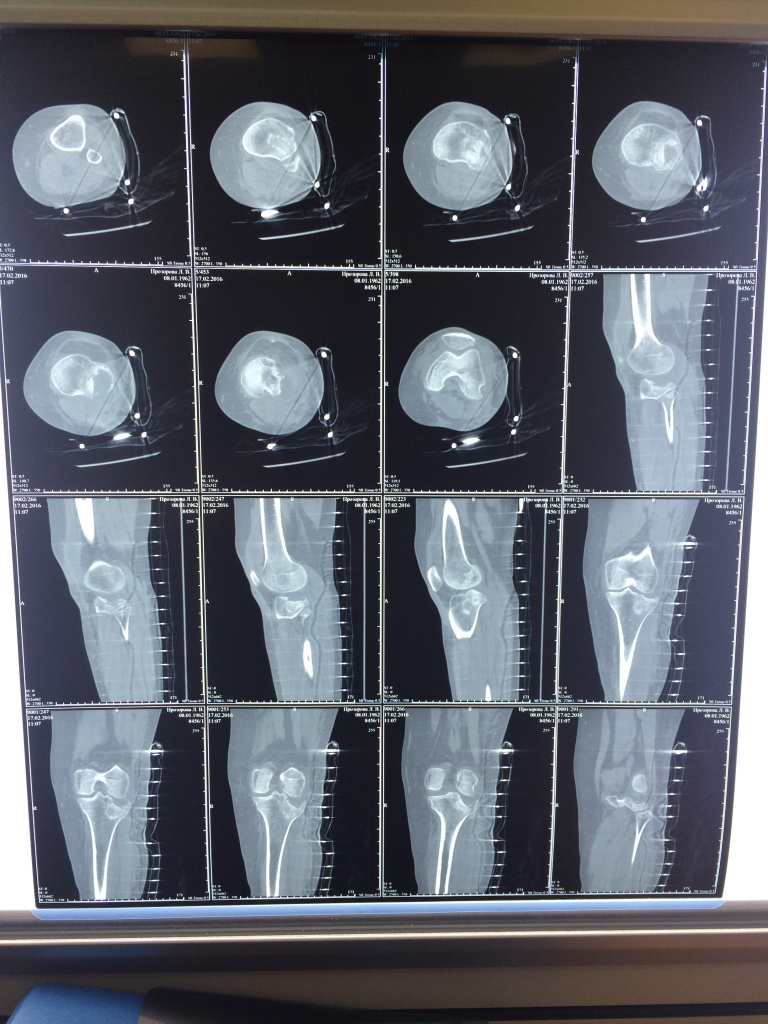

Использование материала Остеоматрикс при импрессионном оскольчатом переломе наружного мыщелка большеберцовой кости по типу Schatzker II

Использование материала Остеоматрикс при импрессионном оскольчатом переломе наружного мыщелка большеберцовой кости по типу Schatzker II.

Операция - открытая репозиция, остеосинтез большеберцовой кости опорной пластиной с костной ксенопластикой маетриалом "Остеоматрикс". На контрольных снимках в три и шесть месяцев имеется консолидация перелома, миграции фиксатора нет, имеется остеоинтеграция ксенопластического материала. Функция коленного сустава полная.